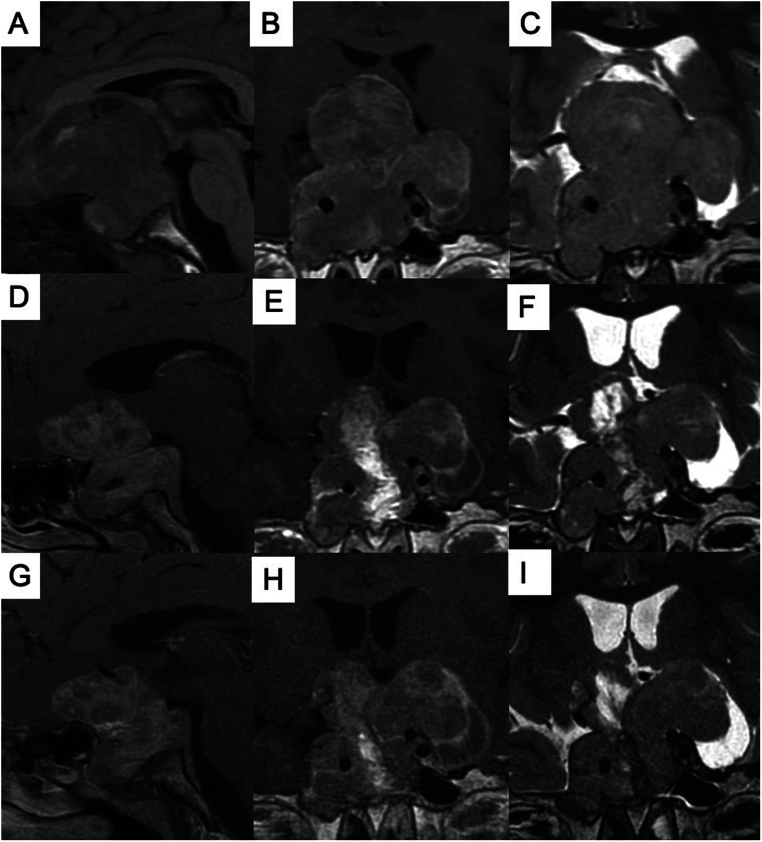

垂体巨人症是一种罕见的儿科疾病,由生长激素(GH)分泌过多引起。近 50% 的病例可以找到遗传原因,其中以芳基烃受体相互作用蛋白(AIP)基因的致病变异最为常见。我们介绍了一例 11 岁男孩的病例,他表现出进行性视力下降,同时伴有线性生长加速和体重增加。经体格检查,他的手掌增大,右眼畸形,身高已超过目标值。GH 和 IGF-I 浓度升高确诊为垂体性巨人症。磁共振成像显示他有一个巨大的蝶窦病变,并有星状上和星状旁延伸。他接受了两次手术,但都未能治愈或改善视力。组织病理学分析显示,肿瘤呈稀疏颗粒状,体生长抑素受体 2 型(SST2)阴性,体生长抑素受体 5 型(SST5)免疫反应评分为 6 分。我们公布的人工智能预测模型预测,患者对第一代体生长抑素受体配体无反应的几率为 83%。因此,我们给他开了帕西洛肽,之后又加用了卡麦角林。IGF-I 浓度有所下降,但并未恢复正常。我们在 AIP 基因内含子 2 的剪接供体区发现了一个新的种系单核苷酸变异(NM_003977.4:c.279+1 G>A),根据美国医学遗传学和基因组学学院指南,该变异被归类为可能致病。

Pituitary gigantism is a rare pediatric disorder caused by excess growth hormone (GH) secretion. In almost 50% of cases, a genetic cause can be identified, with pathogenic variants in the aryl hydrocarbon receptor-interacting protein (AIP) gene being the most common. We present a case of an 11-year-old boy who exhibited progressive vision loss, associated with accelerated linear growth, and weight gain. On physical examination, he had enlarged hands, right eye amaurosis, and was already above his target height. Increased GH and IGF-I concentrations confirmed the diagnosis of pituitary gigantism. Magnetic resonance imaging showed a giant sellar lesion with supra- and para-sellar extensions. He underwent two surgeries which did not achieve a cure or visual improvement. Histopathological analysis revealed a sparsely granulated tumor, negative for somatostatin receptor type 2 (SST2) and an immunoreactivity score of 6 for somatostatin receptor type 5 (SST5). Our published artificial intelligence prediction model predicted an 83% chance of not responding to first-generation somatostatin receptor ligands. Pasireotide was therefore prescribed, and afterward cabergoline was added on. IGF-I concentrations decreased but did not normalize. We discovered a novel germline single nucleotide variant in the splicing donor region of intron 2 of the AIP gene (NM_003977.4:c.279+1 G>A), classified as likely pathogenic according to the American College of Medical Genetics and Genomics guidelines.